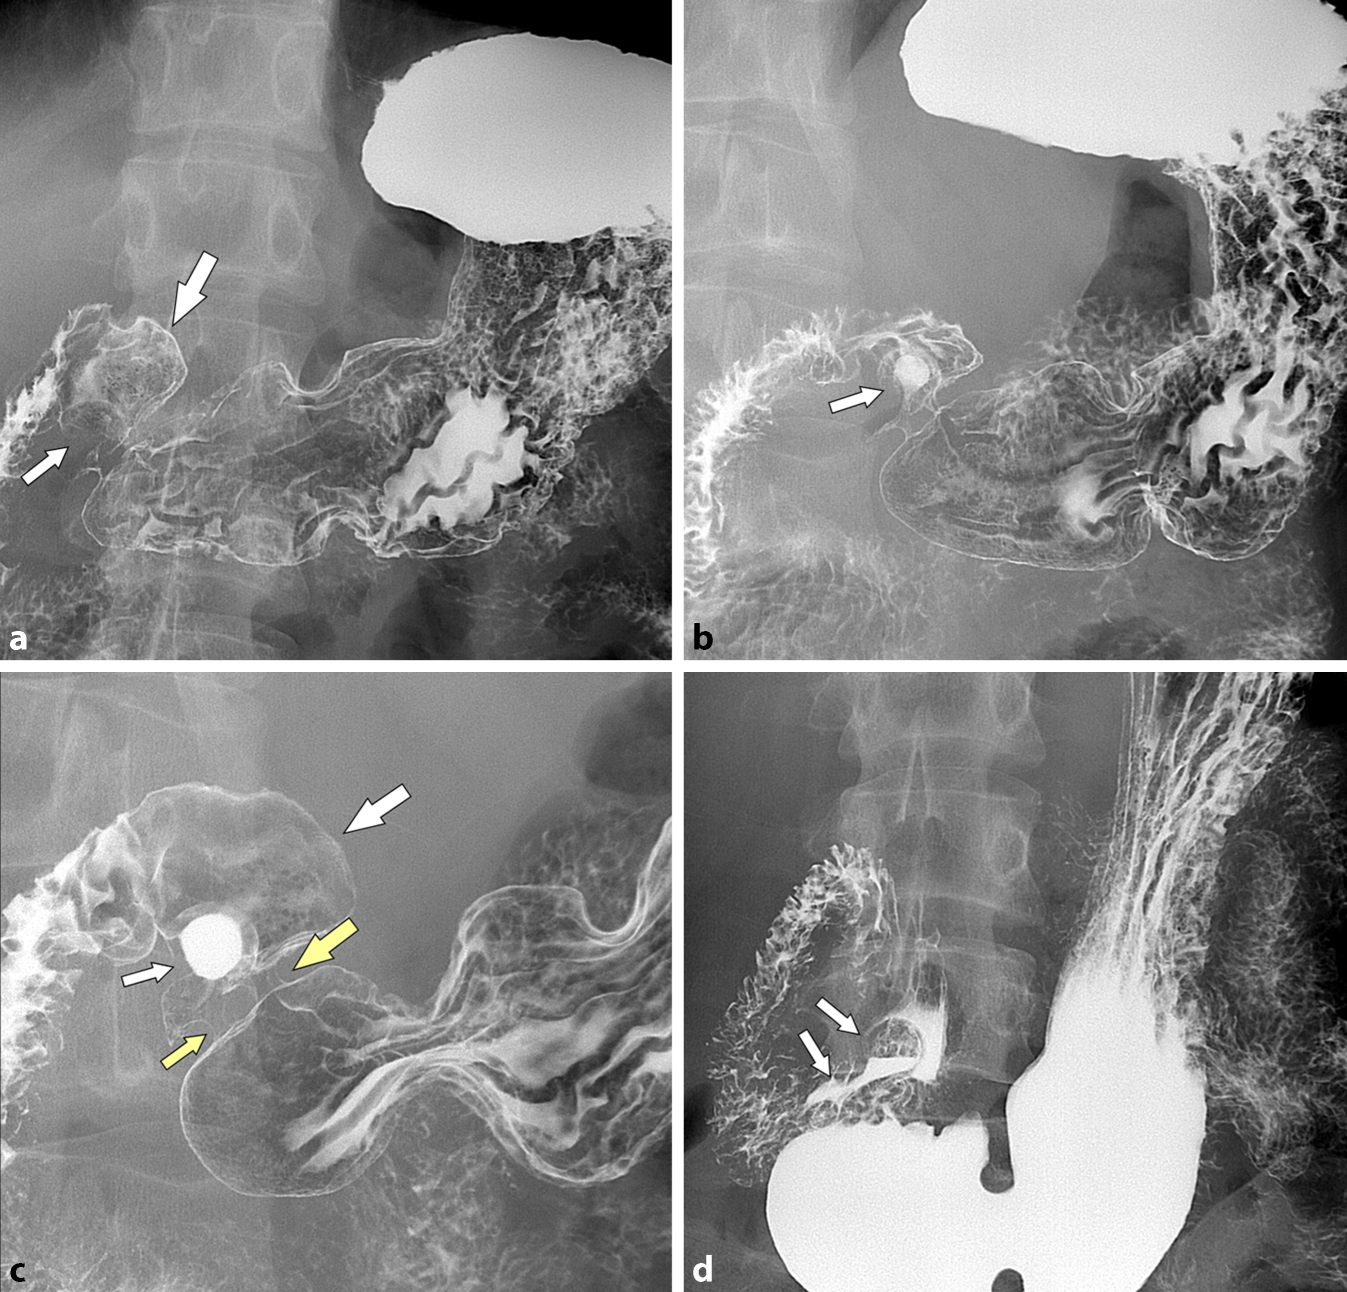

Abb. 2

a Das Magen-Duodenum-Röntgen im Doppelkontrast zeigt einen gut entfalteten Bulbus duodeni (großer Pfeil) mit einer submukösen Raumforderung am Recessus inferior (kleiner Pfeil). b Wenige Sekunden später füllt sich die submuköse Raumforderung mit Kontrastmittel (kleiner Pfeil), was den zystischen Charakter beweist. c Die Vergrößerungsaufnahme zeigt nicht nur die Kontrastmittel-gefüllte dickwandige Zyste, welche den Bulbus (großer Pfeil) imprimiert, sondern neben dem Pylorus (großer gelber Pfeil) einen zweiten Pylorus-artigen Kanal (kleiner gelber Pfeil) zwischen Antrum und Bulbus. d In der stehenden Aufnahme erkennt man die rasche Kontrastmittelfüllung der submukösen Zyste (kleine Pfeile), mit einem Barium-Spiegel